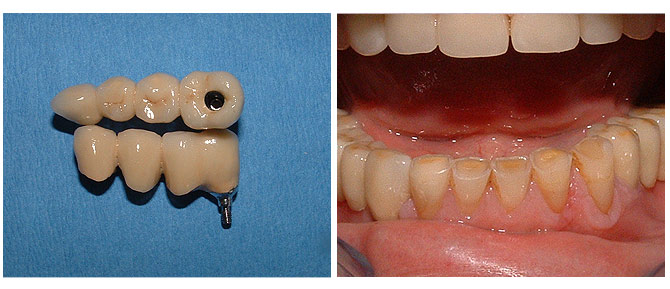

Teilbezahnung

Wenn mehrere Zähne fehlen, ist das Schließen der entstandenen Lücke sehr wichtig. Ansonsten drohen Knochenverlust, Zahn- und Kieferfehlstellungen. Ein großer Vorteil von implantatgetragenem Zahnersatz ist, dass gesunde Nachbarzähne nicht beschliffen werden müssen.